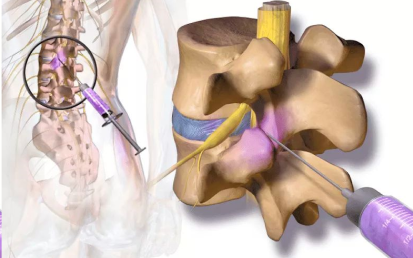

Radiofrequency Ablation may be used in cervical, thoracic, and lumbar spine. It can also be used in the sacroiliac joint and peripheral nerves, where the procedure is employed to reduce pain from the arthritic joints. Radiofrequency Ablation is a technique that employs heat to disable the pain-transmitting nerves in the spine.

The procedure is very safe and is only used on sensory nerves that transmit pain impulses. There is no risk of paralysis or weakness from this procedure. Radiofrequency Ablation uses heat to disable the pain-transmitting nerves in the spine. The process is analogous to microwave ovens that use microwave energy to heat food. Radiofrequency Energy is transmitted to the tip of a needle where it is converted to heat, which is applied directly to the nerve fibers. Once the nerves undergo this heat treatment, they slowly stop transmitting pain.